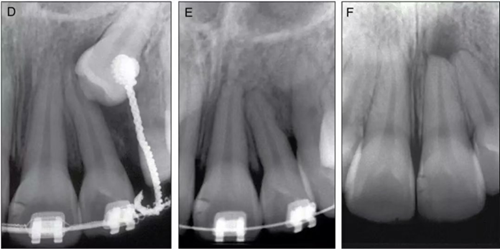

圖1. 患者11歲接受正畸前后及2年后X線片